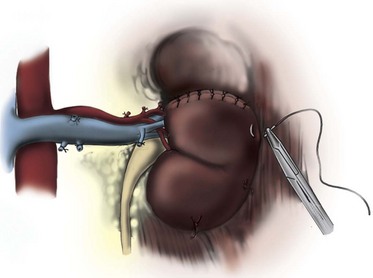

Figure 54–102 A and B, Technique for removing infrahepatic tumor thrombus with assistance of Rummel tourniquets avoiding cardiopulmonary bypass. Ao, aorta; IVC, inferior vena cava; RT. V, right vein.

(© The Lahey Clinic.)

Transesophageal echocardiography is performed before making the incision to evaluate the cephalad extent of tumor thrombus (Fig. 54–102). Radical nephrectomy with removal of a perirenal or infrahepatic IVC thrombus is best approached through a chevron incision. For very large tumors involving the upper pole of the kidney a thoracoabdominal incision may be used instead. Most often these lesions are resected without CPB.

The colon is reflected medially, and a Kocher maneuver is employed to mobilize the duodenum. A Bookwalter retractor is used for exposure. The caudate lobe of the liver can be exposed and a sweetheart retractor placed under it, taking caution to identify and safeguard the porta hepatis. Control of the IVC is obtained with limited manipulation to prevent embolization of tumor thrombus. Rummel tourniquets are placed above and below the thrombus and around the contralateral renal vein (see Figs. 54-103 and 54-104 on the Expert Consult website

Venous occlusion is obtained with the previously placed Rummel tourniquets. An alternative is to use a Satinsky clamp on the IVC and a bulldog vascular clamp on the contralateral renal vein (Novick, 2007). A longitudinal anterior cavotomy is made, and the thrombus is freed from the caval wall to the level of the renal vein ostium using a spatula and gentle manipulation. In most cases the thrombus is not attached to the wall of the cava. The IVC is gently flushed with heparinized saline and evaluated for residual fragments. The infrarenal clamp is released transiently to purge the system of debris and limit the risk of embolus. Alternatively the suprarenal clamp can be released while applying positive pulmonary pressure to flush the cava free of fragments. The cavotomy is closed with a continuous 4-0 polypropylene suture (Figs. 54-105 and 54-106 on the Expert Consult website